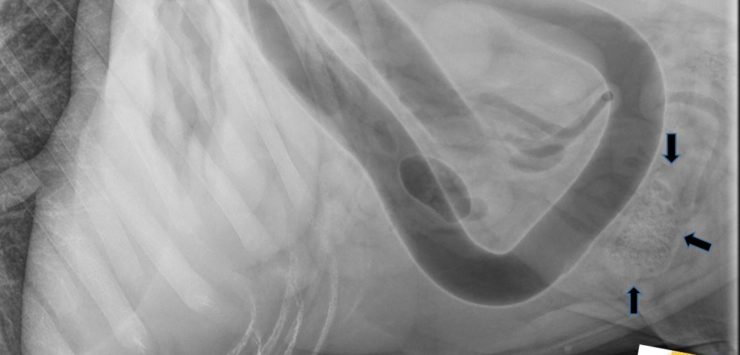

Swallowing the cob or pieces of the cob often causes a life-threatening obstruction of a dog’s gastrointestinal tract, Nelson said, adding that the smaller the dog, the smaller the piece of cob that can cause this to happen. Corncobs also are not digestible, so if there is an obstruction of the gastrointestinal tract, abdominal surgery is usually needed to remove it.

“If smaller pieces of cob are in the stomach, they can sometimes be endoscopically removed,” Nelson said. “But if dogs do not have the cob or pieces of cob causing the obstruction removed, it is usually fatal. Dogs that are brought to a veterinarian after they have been showing symptoms will also sometimes not survive, even with surgery.”